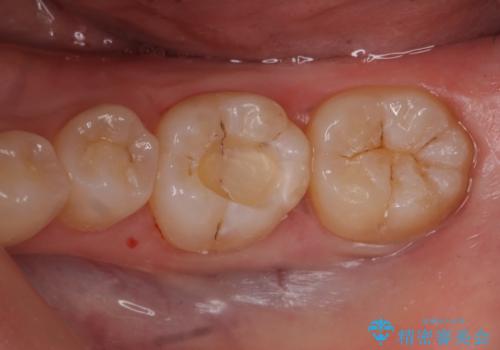

歯が黒いのが気になる

- 奥歯が黒いのが気になるとのことで来院。

レントゲンを確認したところ虫歯が大きくないので、以下の治療の提案を行った。

①虫歯を除去し、CR(レジン樹脂)で埋める。

安価で一日で終わり歯質を削る量が少ないが劣化しやすい(着色しやすい)。

虫歯の再発リスクが高い。

②虫歯を除去し、e-maxインレーで治療する。

歯質を削る量がCRで治療するより多く、また来院回数も多くなる(2回)。

劣化しにくく、虫歯の再発リスクが少ない。

コストがかかる。

患者様と相談し、虫歯が小さい段階で再発リスクの少ない治療を行いたい。

劣化も避けたいとのご希望だった。

そのため②のe-maxインレーでの治療の方針になった。